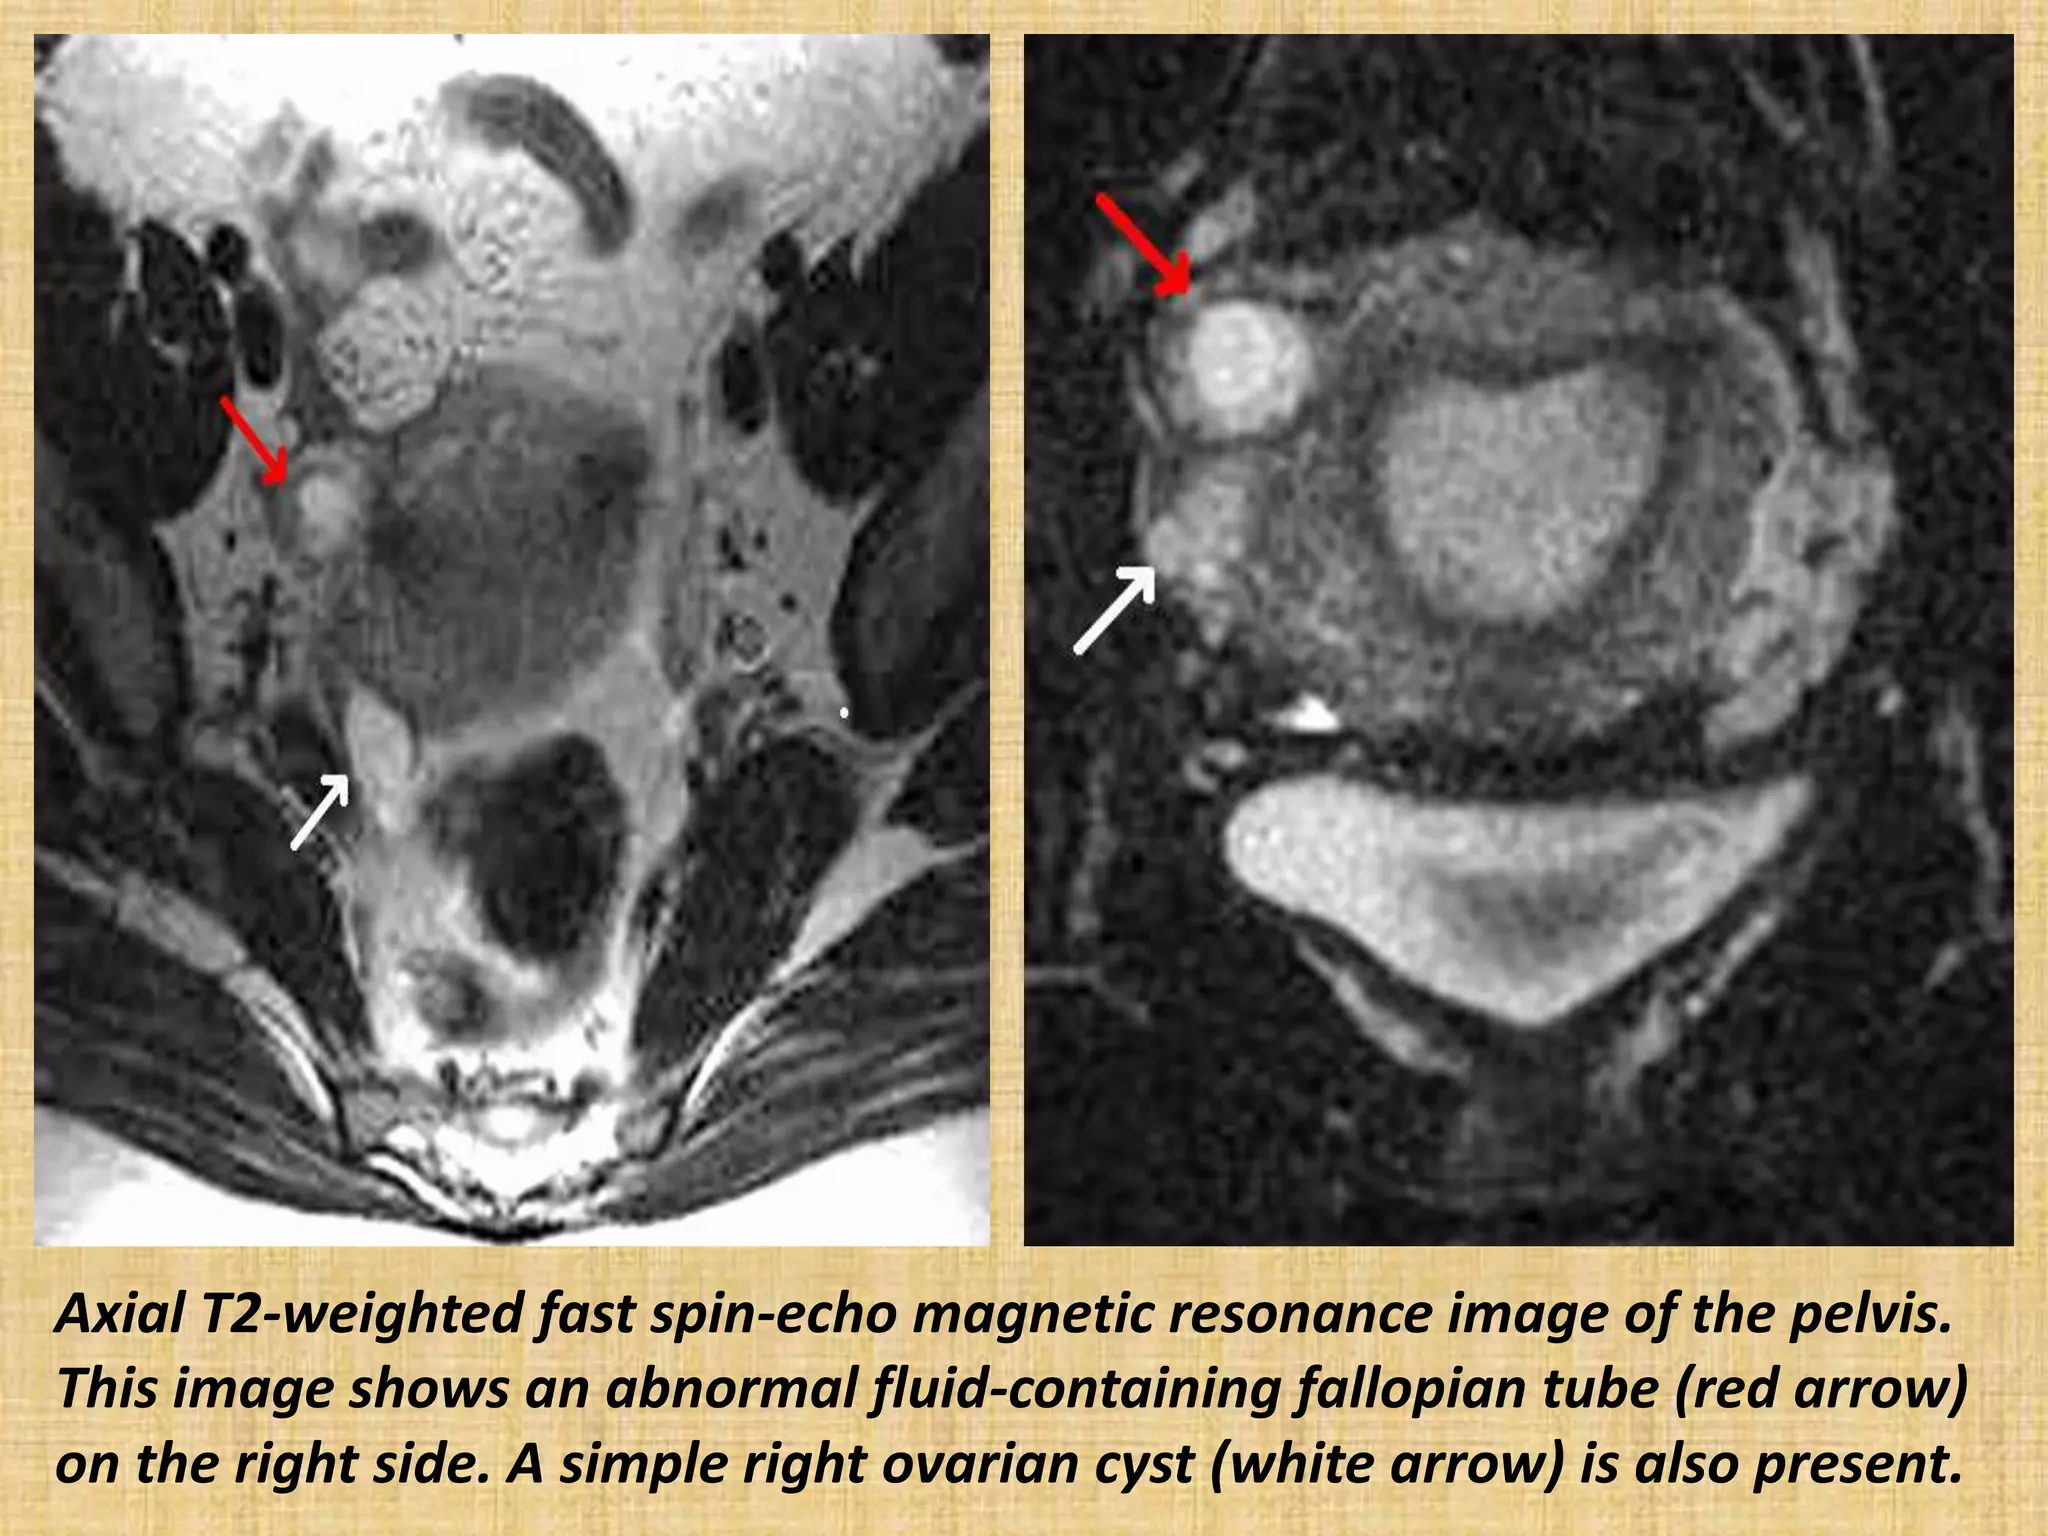

Axial T2-weighted fast spin-echo magnetic resonance image of the pelvis.

This image shows an abnormal fluid-containing fallopian tube (red arrow)

on the right side. A simple right ovarian cyst (white arrow) is also present.

Axial T2-weighted fastspin-echo magnetic resonance image of the pelvis. This image shows an abnormal fluid-containing fallopian tube (red arrow) on the right side. A simple right ovarian cyst (white arrow) is also present.